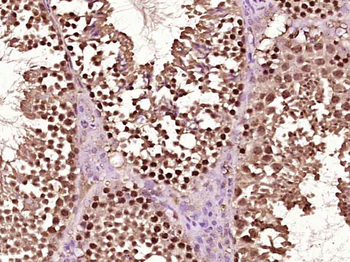

RARB Rabbit Polyclonal Antibody [orb11327]

FC, ICC, IF, IHC-Fr, IHC-P, WB

Bovine, Canine, Gallus, Porcine, Rat

Human, Mouse

Rabbit

Polyclonal

Unconjugated

50 μl, 100 μl, 200 μlTIG2 Rabbit Polyclonal Antibody [orb11481]